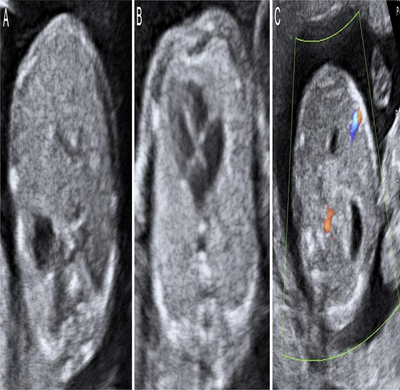

Ecografía Obstétrica

Ecografía 3D y 4D